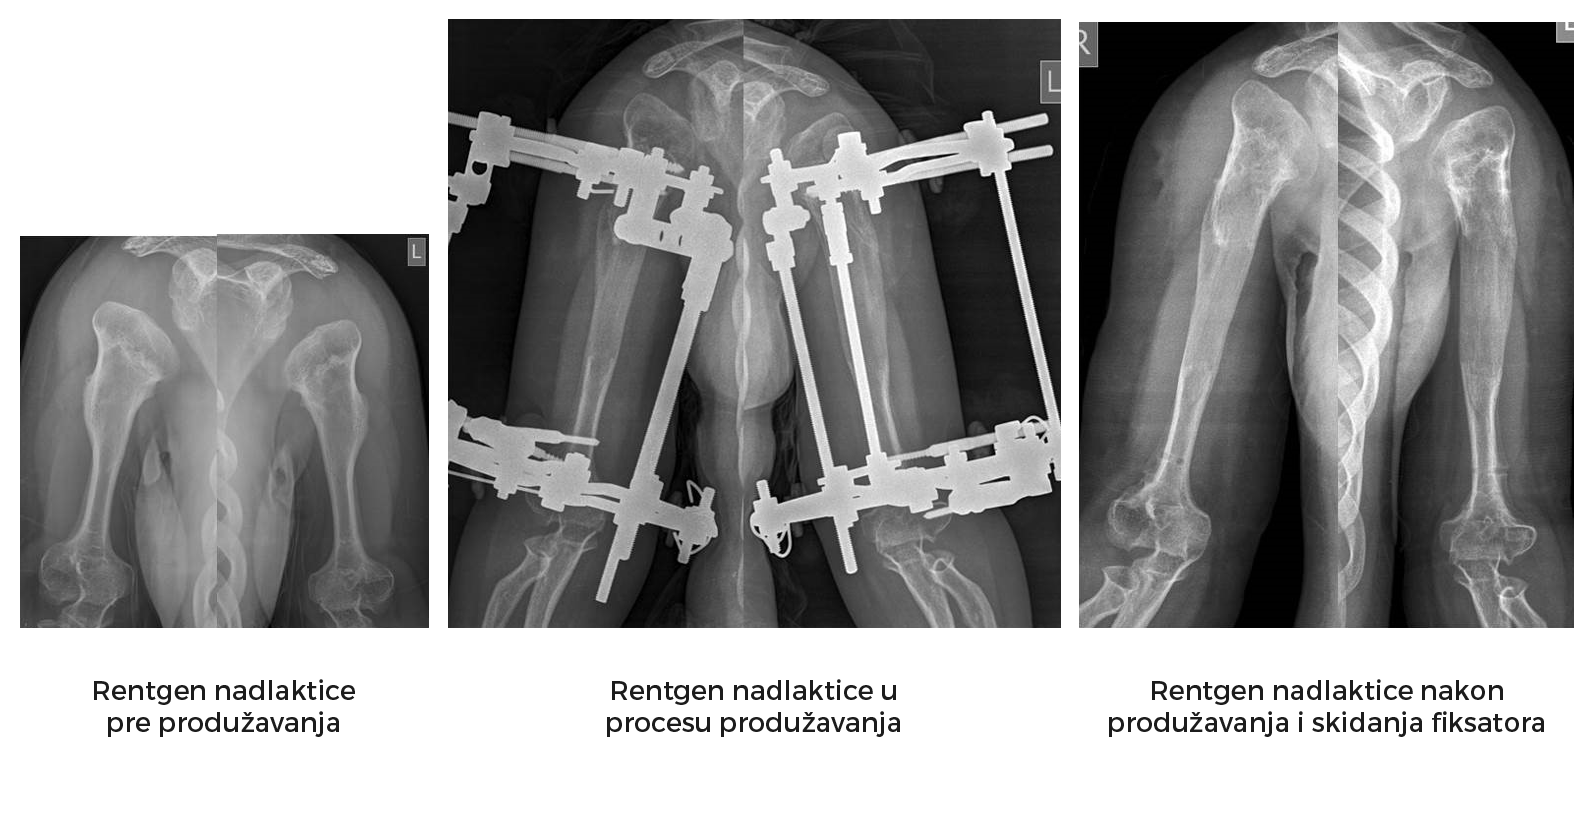

*Etapa produžavanje nadlaktice.

Slede primeri takve rekonstrukcije ekstremiteta (iz arhive prof. D. Popkova i Atlas klinike).